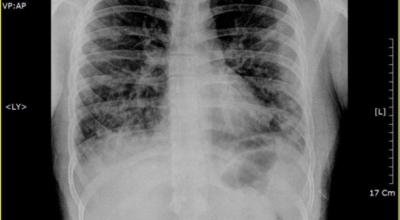

폐렴 증상이 있는 경우 X선 촬영 및 배양 검사로 진단할 수 있답니다. 필요에 따라 소변, 혈액, 혈청 검사, CT 등을 추가로 실시합니다. 폐렴 진단을 받은 환자는 일반적으로 입원을 권장하지 않지만 젊거나 기초질환이나 호흡곤란이 심한 경우, 고령, 임신 등의 경우 병원에 내원하여 상황에 맞는 신속한 치료와 상태 개선, 위험관리를 받는 게 좋아요.